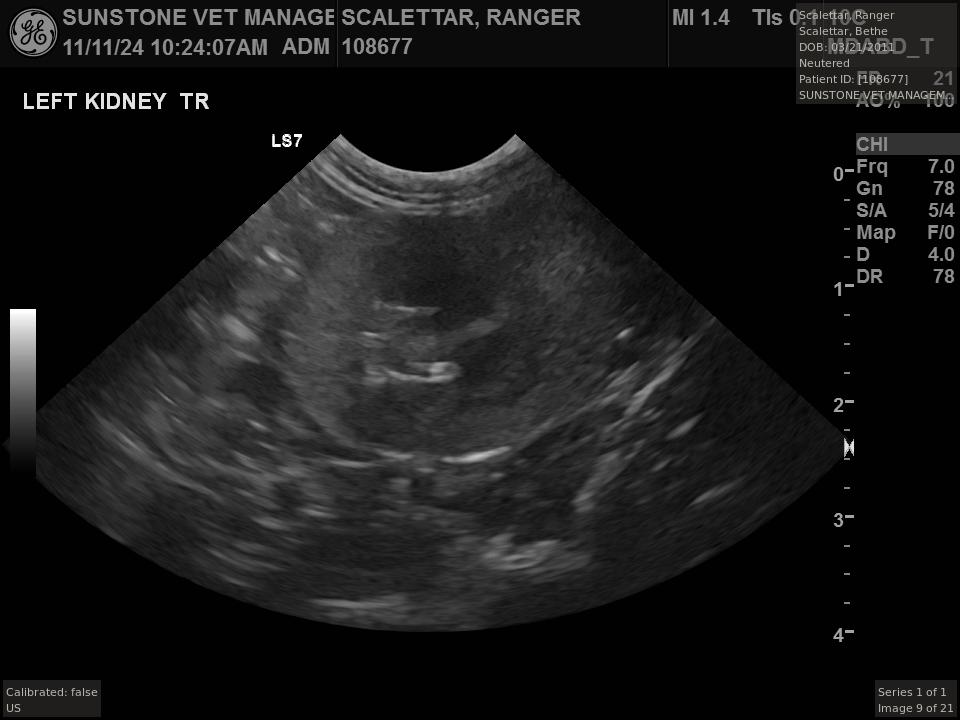

The veterinarian generated a series of images showing different organs and substructures by

changing the position and orientation of the ultrasound transducer. The images were collected

in a defined order, which is repeated from patient to patient, ensuring that nothing is missed. In

Ranger's case, the sonographer collected about twenty images during an examination that

lasted about fifteen minutes.

The sonographer stated that Ranger's ultrasound images were largely normal for an older cat. In particular, they show changes in the kidneys that are commonly noted in geriatric cats and that reflect a risk for the development of chronic kidney disease. However, the images did not show any significant abnormalities in Ranger's stomach, intestines, and associated lymph nodes. Nonetheless, the results did not rule out recurrence of Ranger's small cell lymphoma.